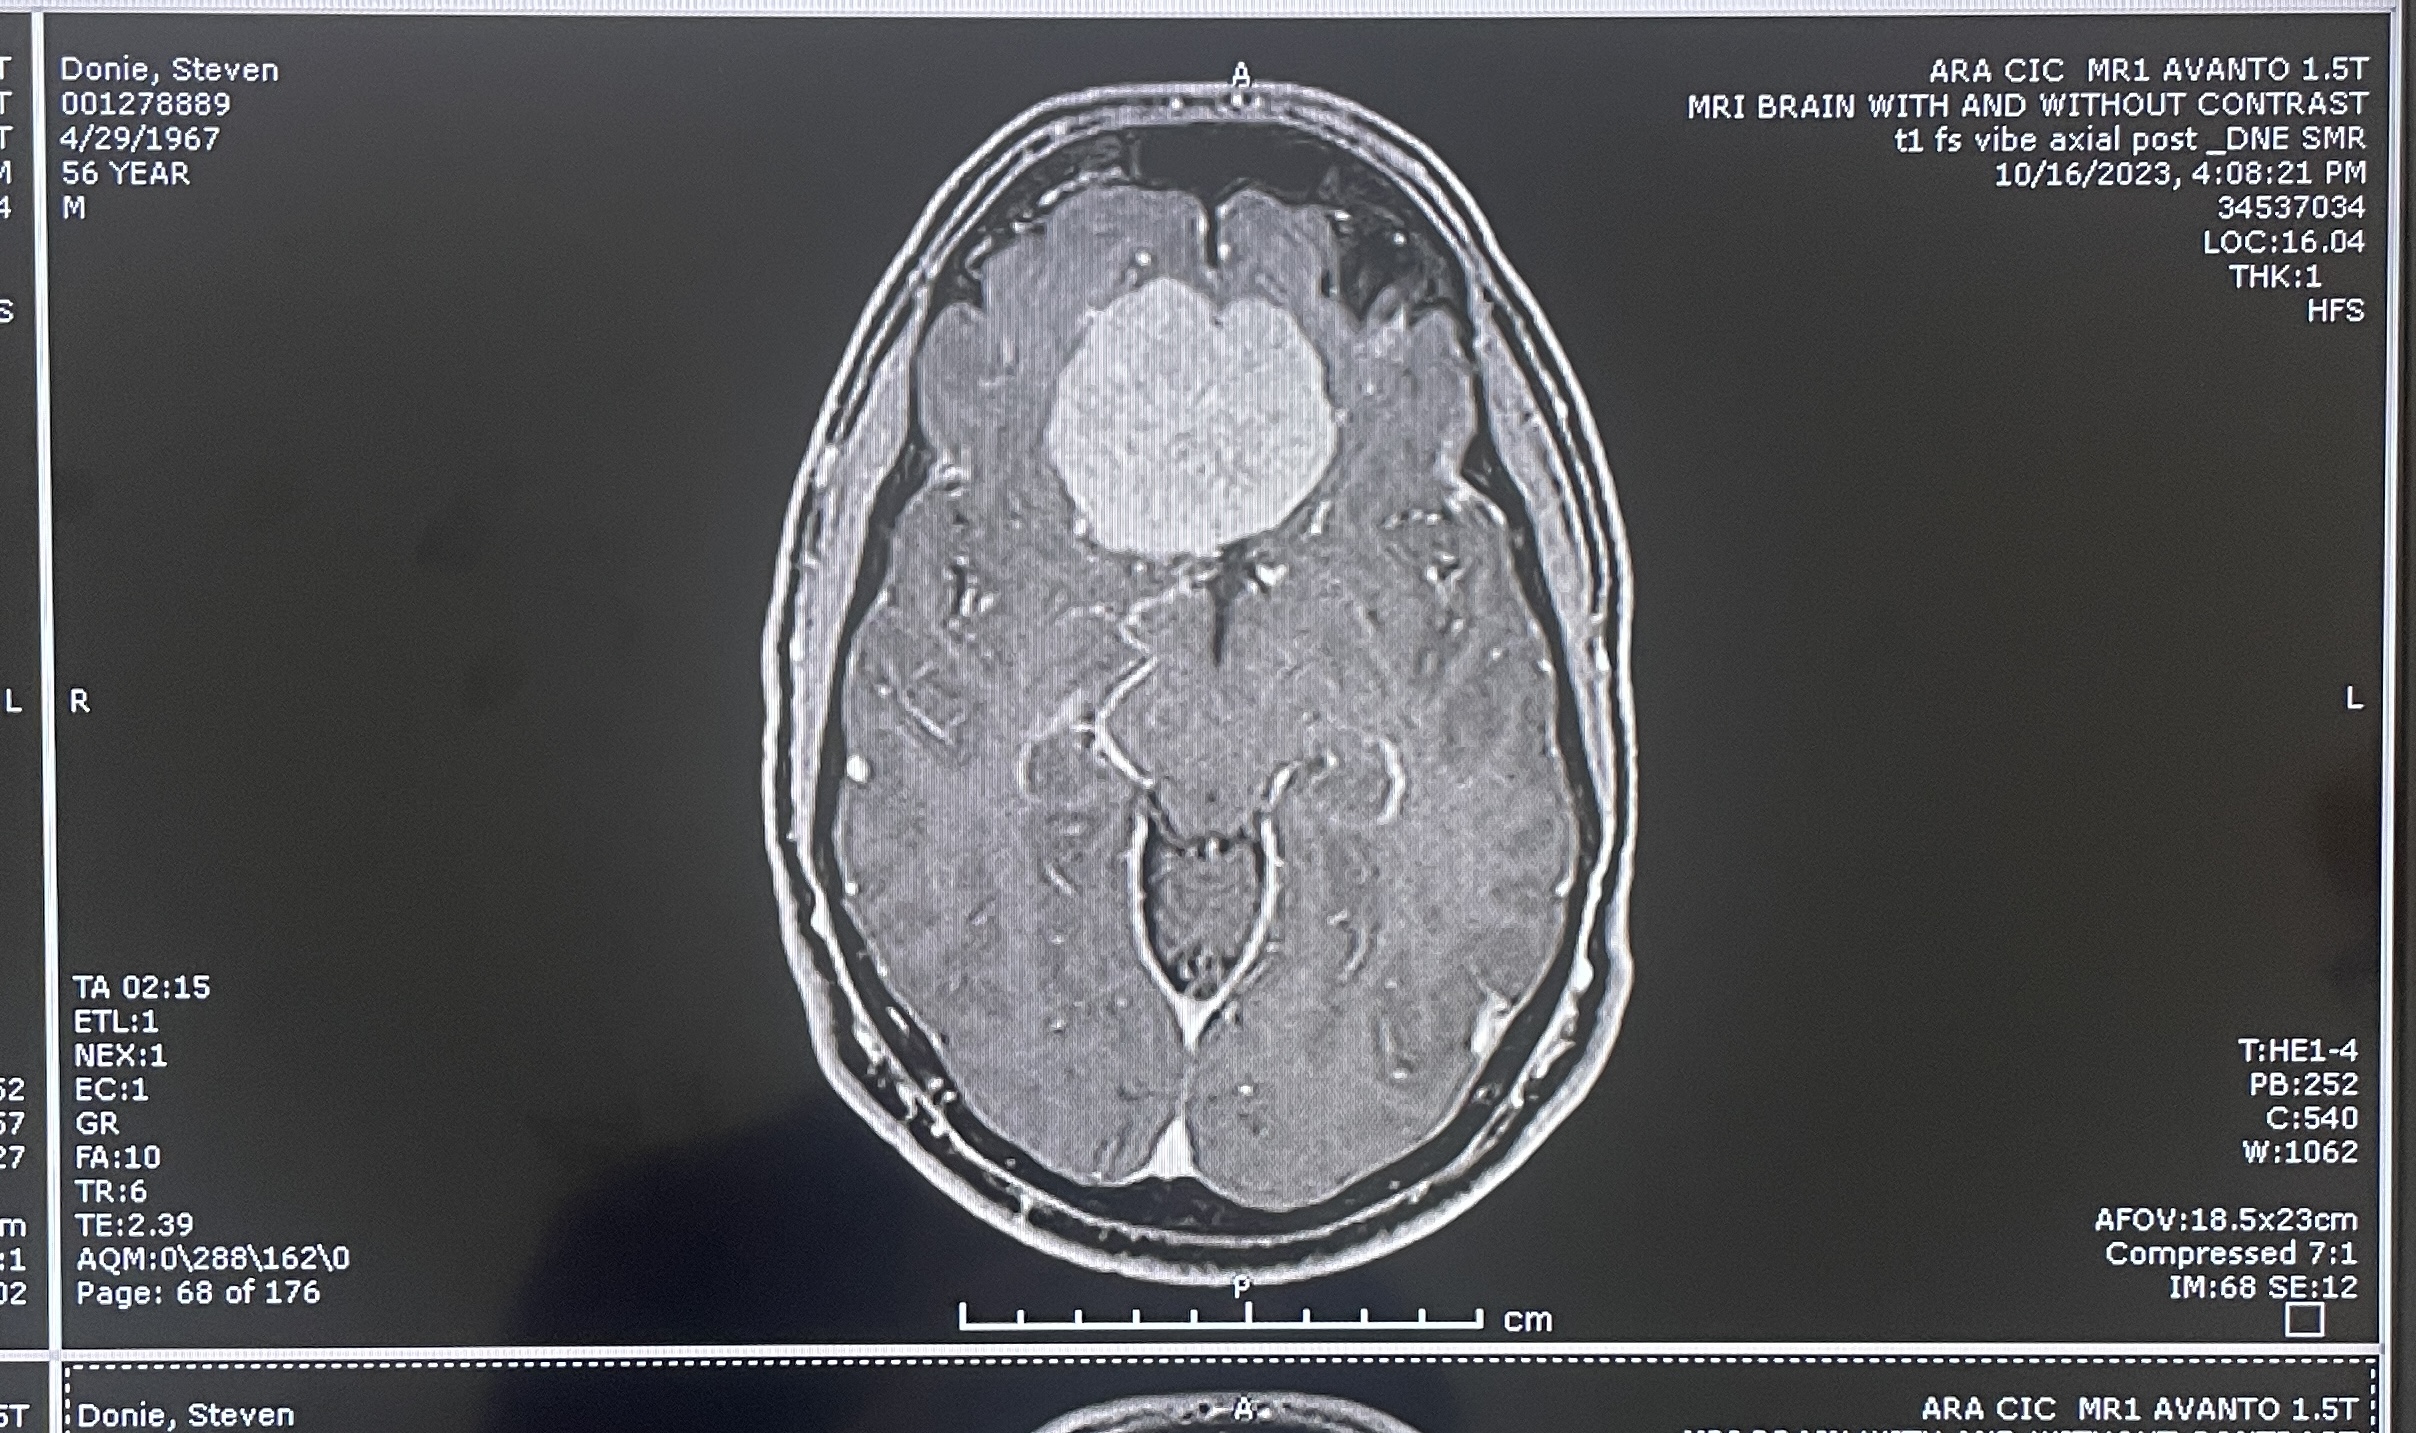

Another clear top view

more MRI